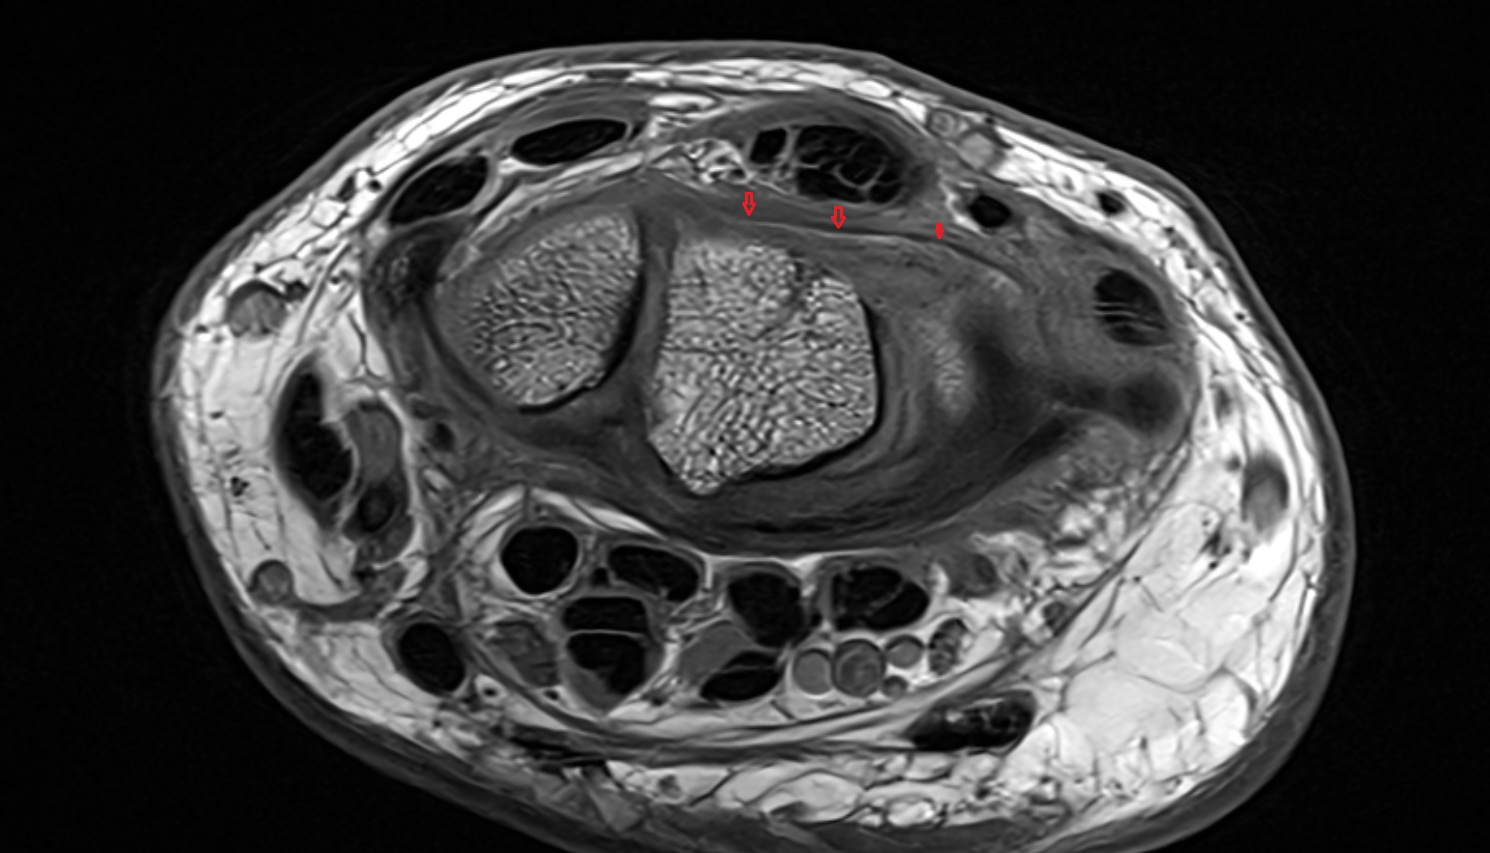

- Knee Joint